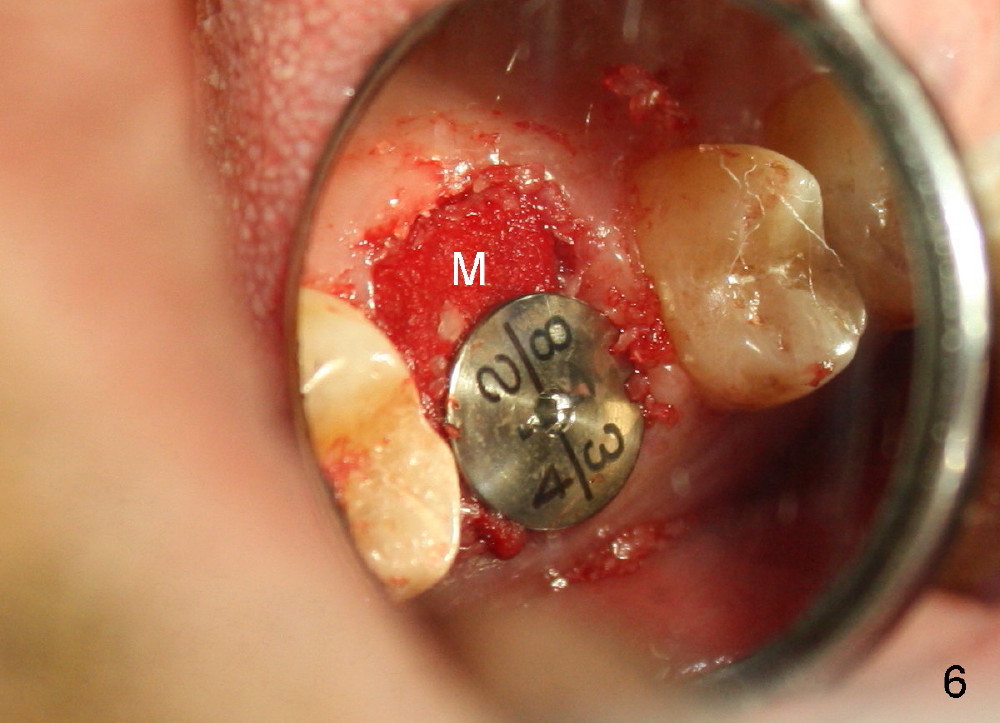

The tooth #3 has a crack line (Fig.1 ^). The septum (Fig.2 S) looks like an inverted pyramid (Fig.3), coronal part being pointed, whereas the apical broad. The shape of the septum is not so favorable to placement of tapered implant. Osteotomy starts with 1.5 mm pilot drill in the middle of the septum, followed by round tapered osteotomes 2 and 3 mm. The osteotomy begins to deviate into the mesiobuccal socket. The same osteotomes are used to re-direct the osteotomy palatally, followed by tapered drills, trying to move osteotomy palatally. A 4.5x17 mm tap is inserted with stability (Fig.4). Following using 5x17 mm tap at the depth of 12 mm, a 5.3x12 mm bone-level implant is placed ~ 1.5 mm below the crest, 1.5 mm above the septum (Fig.5). Demineralized cortical human allograft is placed in the remaining sockets and around the most coronal aspect of the implant (with a small piece of gauze placed in the implant well). After removal of the gauze, a piece of collagen membrane is pierced and carried by a 8.2x4/3 mm healing abutment and fixed in place (Fig.6 M). The periphery of the membrane is tucked underneath the gingiva. The wound is covered by perio dressing. The patient returns to clinic for follow up 8 days postop. There is no discomfort. In order to protect the collagen membrane (Fig.6), the perio dressing is intentionally not removed (Fig.7). Two weeks postop, the patient remains asymptomatic. After perio dressing removal, the membrane appears to have been resorbed (Fig.8 as compared to Fig.6). The bone graft (B), although exposed, remains in place and condensed, surrounded by healing healthy gingiva (*). The patient returns 2.5 months postop. The implant appears to osteointegrate (Fig.9, as compared to Fig.5). The buccal (Fig.10) and palatal (Fig.11) gingiva adapts to the healing abutment. When the healing abutment is removed for restoration 3 months postop, the gingiva looks healthy (Fig.12). A cemented abutment (5.8x4(2) mm) is placed; a crown is fabricated (Fig.13). The patient returns for recall 5 months post cementation. He reports food impaction distal to the crown. The gap mesial to the implant has closed (Fig.14).